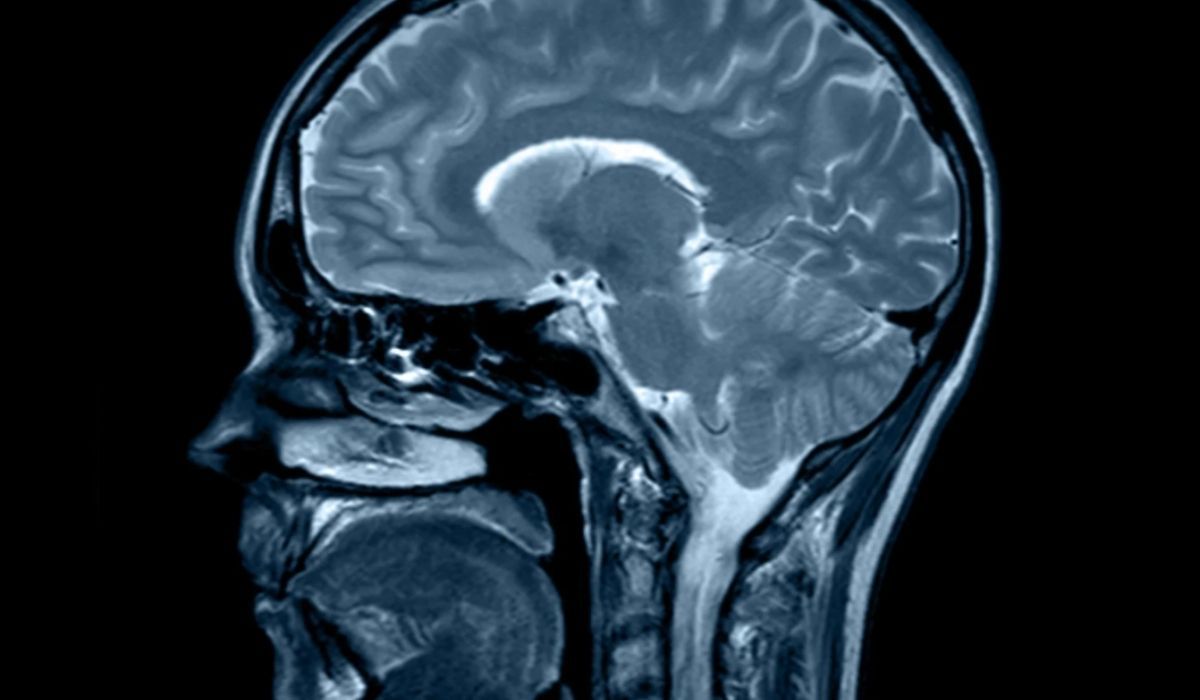

Neurolodzy przyznają, że zawroty głowy należą do najbardziej złożonych zagadek ambulatoryjnych. Badania obrazowe mózgu, testy równowagi czy laryngologiczne oceny słuchu często niczego nie wykazują. Subiektywny charakter objawu, jego zmienność w czasie oraz wpływ stresu dodatkowo zaciemniają obraz. Lekarze rodzinni, tacy jak dr Dean Eggitt, mówią wprost: „kiedy przychodzi pacjent z zawrotami, trzeba przejść dziesiątki scenariuszy, bo jedna przyczyna potrafi ukrywać się pod objawami innej”. W efekcie proces dochodzenia do rozpoznania bywa dłuższy niż w przypadku bólu głowy czy bólu w klatce piersiowej, a pacjent nierzadko odchodzi z nic nie mówiącym zaleceniem „obserwacji”.